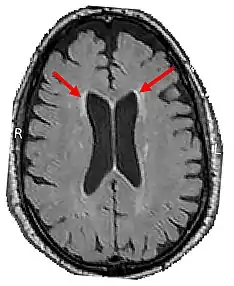

LENAS is seen with damage to the white matter and axons within the brain. The external human LENAS brain shows findings in several major structures. There is mild atrophy of the frontoparietal regions of the brain and a mild reduction of the thalamus and rostral (front) part of the caudate nucleus (which is located in an area of the brain called the basal ganglia).[4] Abnormalities in the frontal, frontoparietal, and temporal lobes are most severe and predominant with LENAS and asymmetry of the cerebral hemispheres has sometimes been found.[4] LENAS also may show moderately enlarged lateral ventricles and atrophy in corticospinal tracts as well as in the pons.[4]